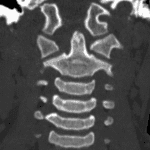

- No acute fracture

- Rotation of C1 on C2 with asymmetry of the lateral atlantodental intervals on coronal and axial images

- Atlantoaxial rotatory fixation

No acute fracture.

Rotation of C1 on C2 with asymmetry of the lateral atlantodental intervals on coronal and axial images. While this finding could relate to patient positioning, atlantoaxial rotatory fixation could have a similar appearance. Consider MRI to exclude ligamentous injury.